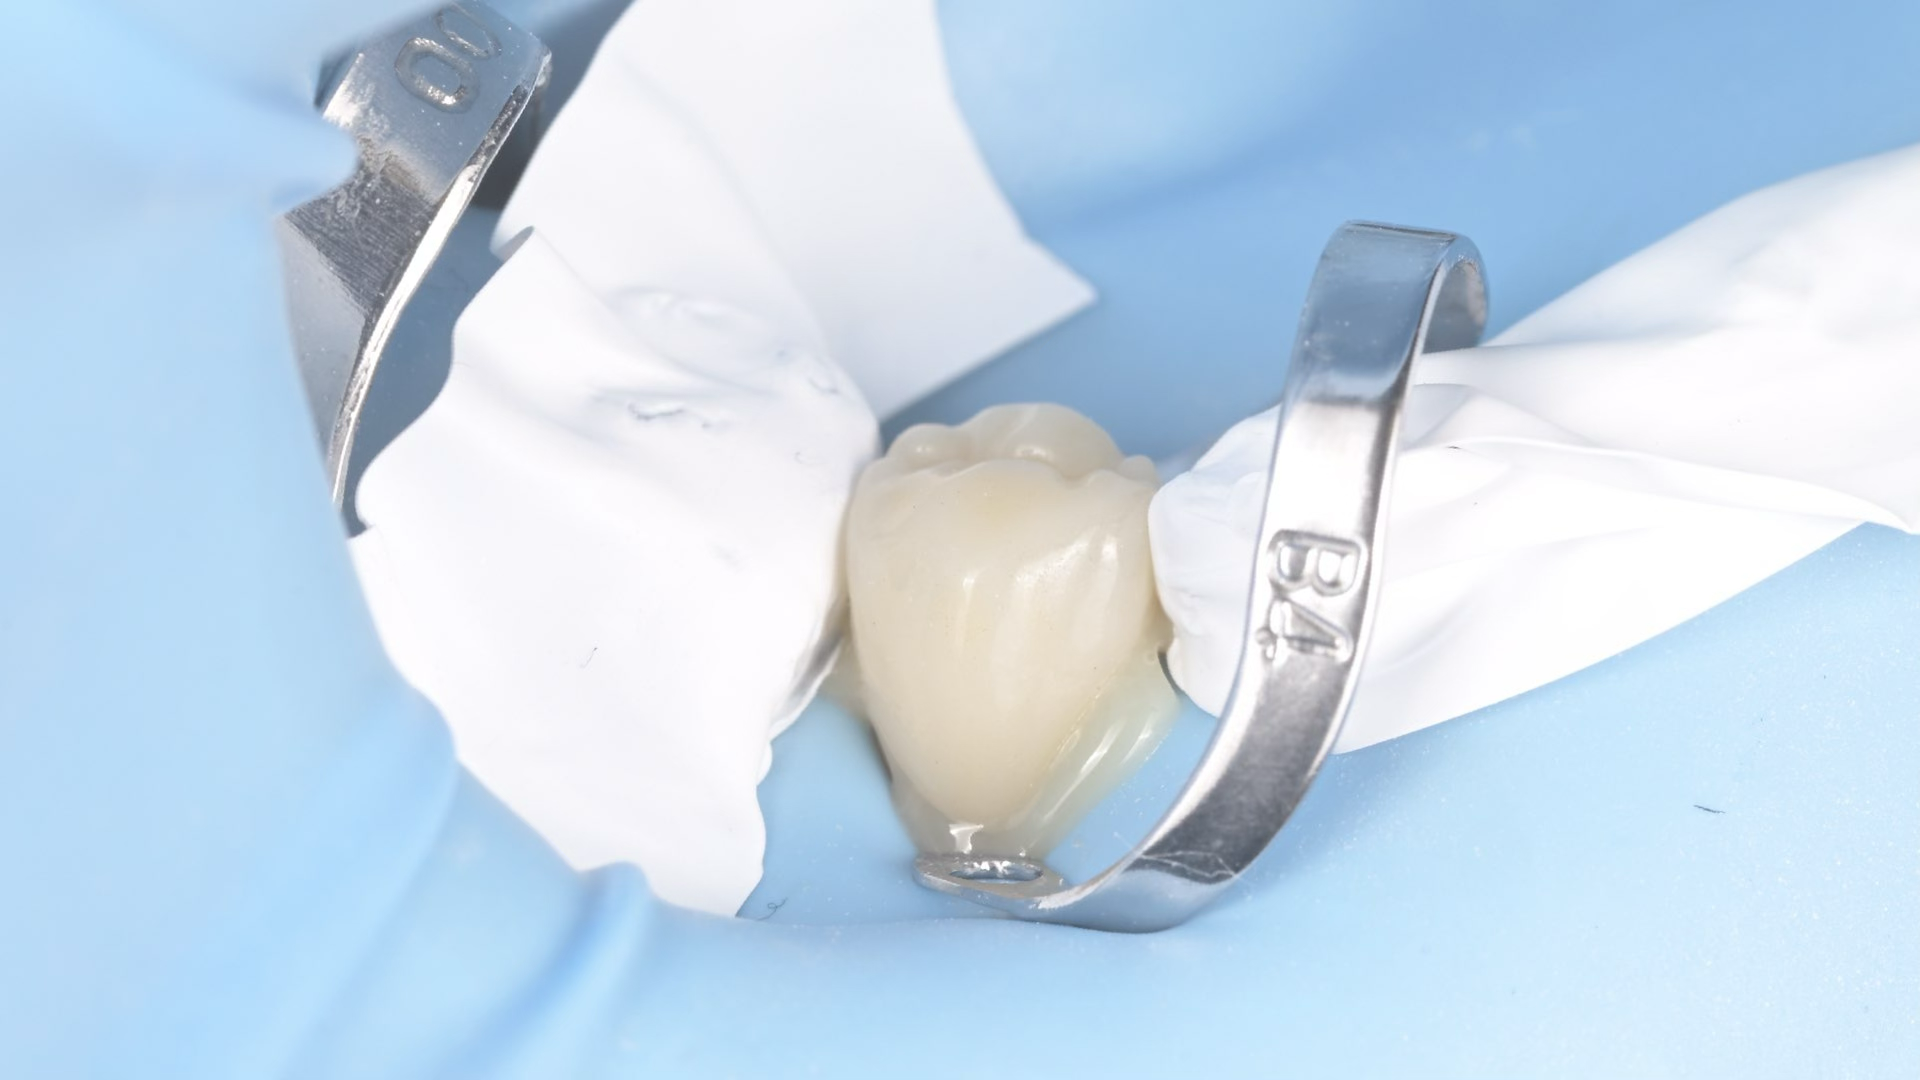

A biomimetikus fogászat egy modern megközelítés, melynek célja, hogy a fogak helyreállítását a fogorvos a természetes fog szerkezetét utánozva végezze el. A módszer kulcsa, hogy a fogat a lehető legkevésbé invazív módon kezelje, maximalizálva a megmaradt egészséges fogszövetet.

Célja, hogy az elkészült tömések és betétek (inlay, onlay) ugyanolyan erősek és rugalmasak legyenek, mint a természetes fog.

Ennek eléréséhez speciális ragasztási technikákat és bio-kompatibilis, üvegszál-erősítésű anyagokat használnak, melyek szorosan kötődnek a foghoz.

A hagyományos koronázással szemben, ahol sok ép foganyagot kell eltávolítani, a biomimetikus eljárásnál csak a sérült részeket távolítják el.